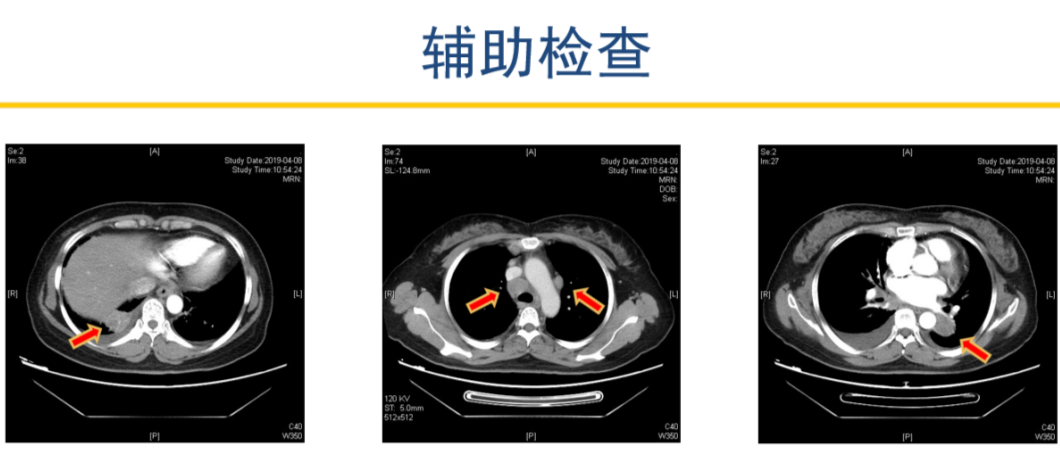

患者2019-04-08 胸部增强CT,显示左肺下叶占位并纵隔、双肺门、右锁骨上多发肿大淋巴结,考虑肺癌可能。右下肺占位,建议抗炎治疗后复查。

2019-04-12 PET-CT显示①右肺下叶后基底段胸膜下软组织密度肿块(大小26*30mm)。

②左肺下叶纵隔旁软组织密度肿块(大小28*31mm)。

③双肺门、纵隔内隆突下、气管旁、主肺动脉窗、血管前间隙、右侧颈部Ⅴ区及锁骨区多发增大淋巴结。